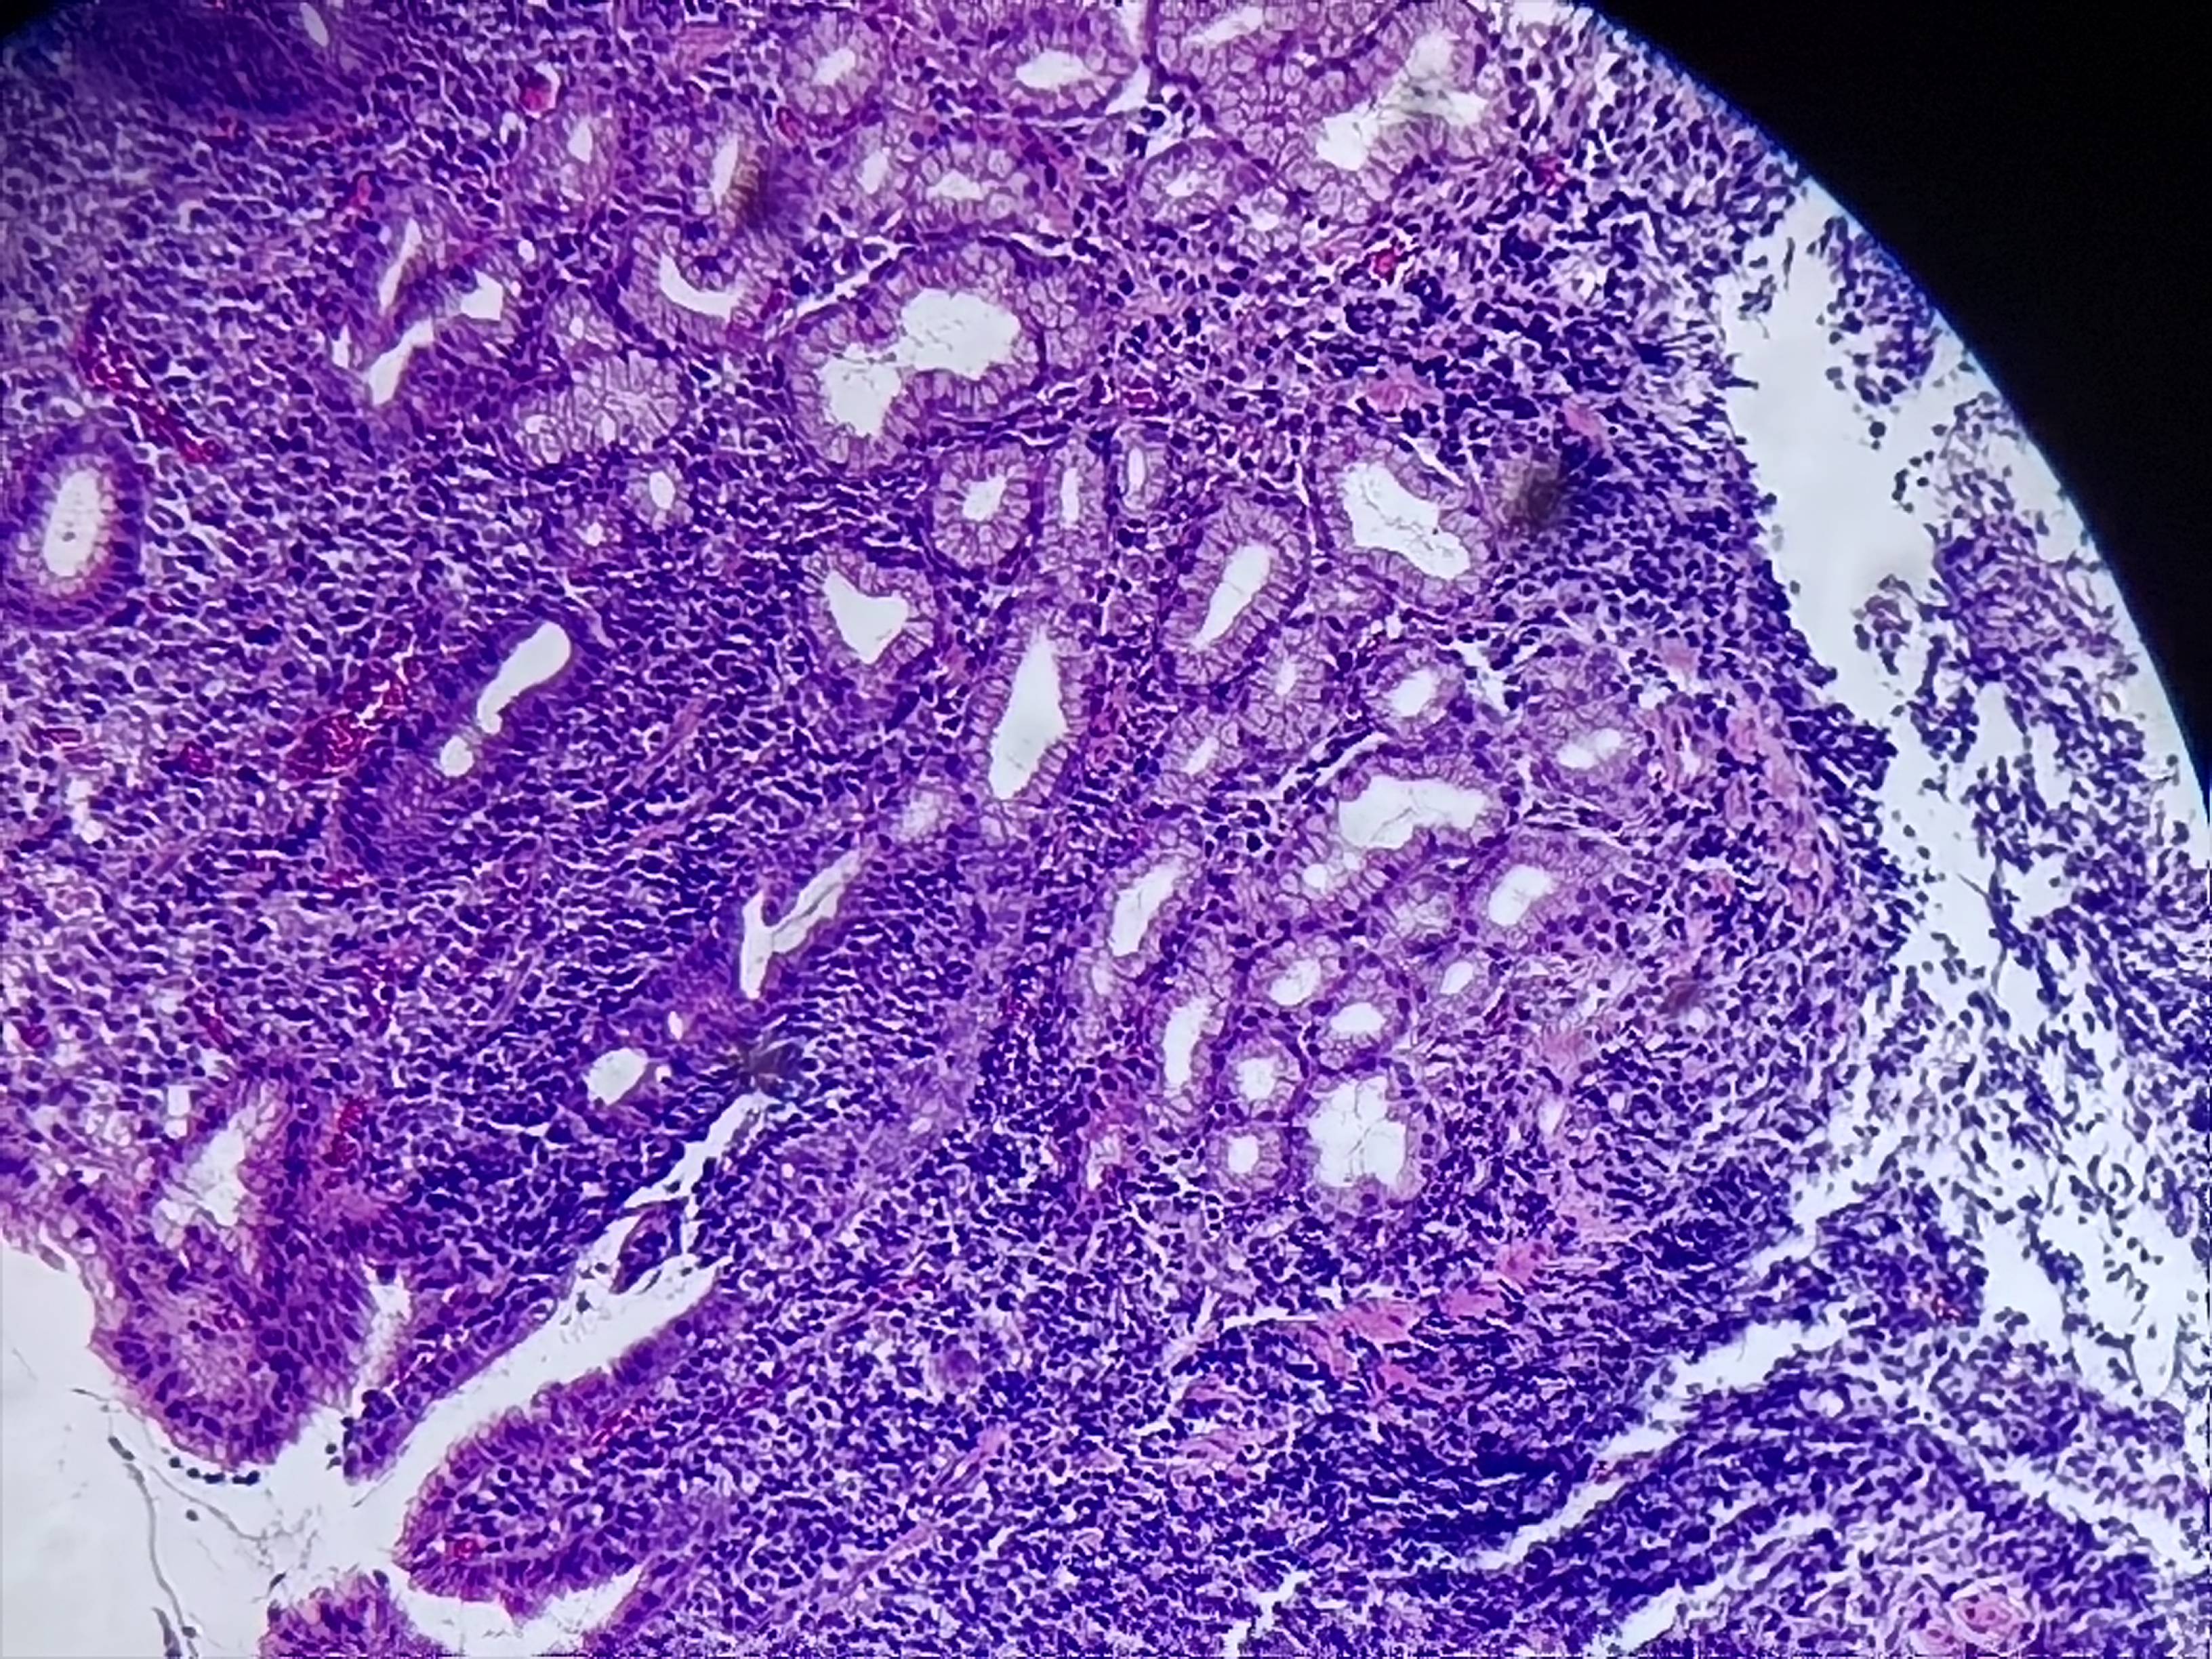

胃角活检

性别

男

年龄

60岁

临床诊断

慢性萎缩性胃炎伴糜烂

一般病史

胃角前壁粘膜凹陷

标本名称

胃角粘膜活检

大体所见

灰白色组织1块

慢性炎伴糜烂。

加做个免疫组化除外淋巴瘤